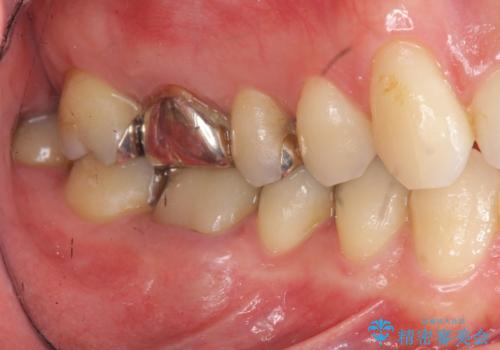

矯正と虫歯のセラミック治療 総合歯科治療の実践

- 突き出た前歯の角度の改善と虫歯治療の改善を求めて来院されました。

虫歯を除去したのち、マウスピース矯正治療を行い、歯並びやがたつきを改善したのち、セラミックに置き換えることで審美性の向上を計画します。